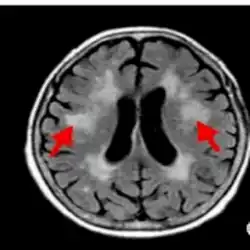

- Fluid-attenuated inversion recovery (FLAIR) uses a pulse sequence to suppress cerebrospinal fluid and show lesions more clearly, and is used for example in multiple sclerosis evaluation.